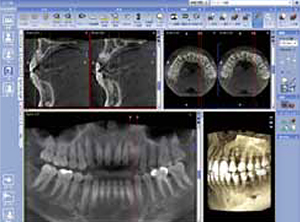

CT撮影 3D画像による診断

当院では歯科用CT「プロマックス3DS」を導入しております。インプラント治療において、正確な診断と安全確実な治療のために歯を支えている周りの骨の状態、神経の位置などを知ることはとても重要です。これからのインプラント治療にCT撮影・診断はかかせません。

従来のCT撮影をする場合、患者さまご自身に大学病院などCTを設置している総合医療施設まで通っていただく必要がありました。装置も医科用の大型のもので断層幅も大まかで、データ解析にも時間を要していたことから、気軽に撮影できるとは言えず、患者さまにもご負担がかかっていました。

院内に歯科用CTを導入することでこれらのストレスがなくなりました。医科用CTよりも精度が高く、即座にシミュレーションが可能、通常のレントゲン撮影と同じ感覚で座ったまま気軽に撮影、といった特徴があります。

3次元シミュレーション シムプラント

シムプラント(SimPlant)は、CT撮影のデータを再構成した3D画像により、多角的な測定やインプラント埋入シミュレーションを実現します。

下顎管は線描画機能で見やすく表示し、埋入位置までの距離や頬舌的位置が的確に把握できます。

上顎では、複雑な骨形態が明確になるだけでなく、上顎洞炎、嚢胞、粘膜肥厚なども術前に発見しやすくなります。さらに、ソケットリフトやサイナスリフトなどの骨造成治療に必要な骨体積も計算できます。

3Dの立体画像により、分かりやすくご理解いただけます

CT撮影した顎や歯のデータをもとに、さらに詳しい3Dの立体画像で解析し診断使います。インプラントの安全性を語る上でもっとも気を付けなければいけないポイントが神経の位置、血管の位置、上あごにある空洞の位置です。例として、

- 下顎の神経がインプラントを埋入する位置に非常に近い場合

- 上顎の骨が薄く、空洞(上顎洞)に骨造成しないといけない

…等々のようなケースにおいては、術前シミュレーションでより安全な手術を実現することができます。

3Dによる立体画像で、顎の骨の状態が、見た目にも分かりやすくご説明できることと、ドクターにとっても手術のイメージがよりつかめるメリットがあります。

キチンとした情報を患者さまに提示できます

インプラントは口の中にある骨の部分に埋め込んでいきますが、その際に一般的なレントゲンでは2次元的(平面)にしか判断する事ができません。それを3次元的(立体的)にわかりやすくしたものがシムプラントCT診断です。

これを行うことによって、インプラントを埋め込む場所の骨の固さ、大きな神経のあるリスク高い場所の把握、実際に埋め込む場所にきちんと骨があるか…等の情報を手術前に確認することができます。それにより、手術時間の短縮、患者様へのきちんとした手術内容の説明も行うことができます。

これは、あまり派手なことではないですがとても大切な診断だと自分は力を置いています。これをすることで毎回、インプラント治療の手術前シミュレーションをするたびに、新しい治療技術を考えだすことができます。インプラントは手術前の診断でほぼ決まると言っても過言ではないと思います。

このようにきちんと資料を提示してもらえる医師のところで患者様も治療を受けられれば安心だと自分は考えます。